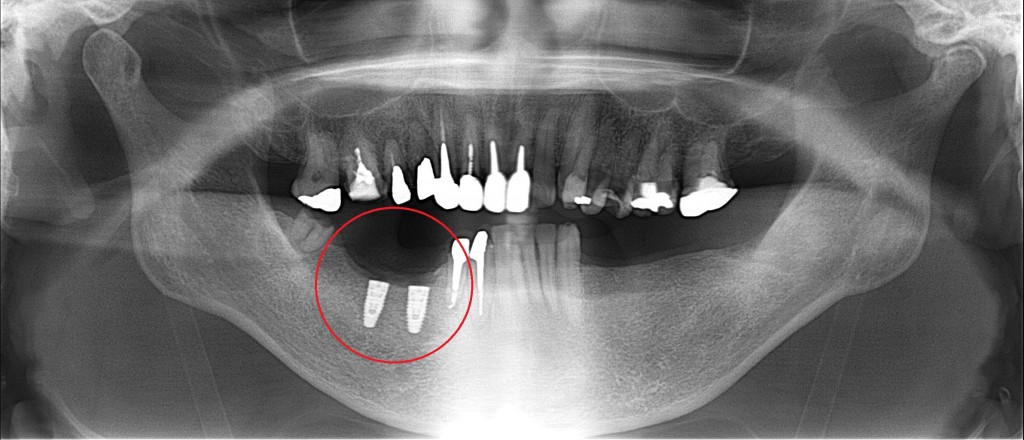

まずは右下の赤い丸の部分に埋入させてもらいました。

上の奥歯と下の歯ぐきが引っ付きそうになっている

長期間、奥歯がない状態だったようで

レントゲンからは分りにくいかもしれませんが

咬んだ時に上の奥歯と下の歯ぐきが

引っ付きそうになっています。